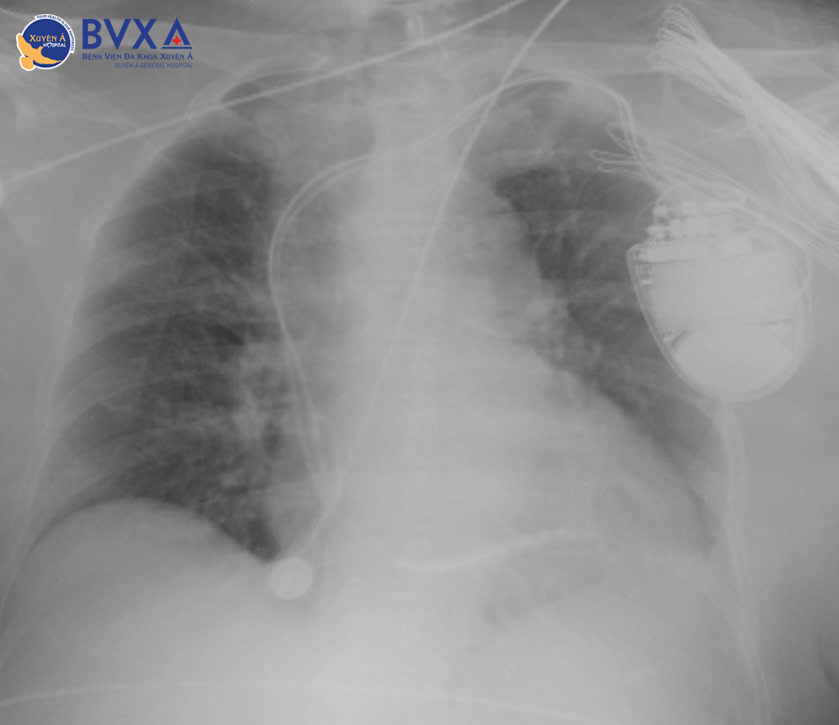

Hình ảnh cận lâm sàng

Trước diễn biến phức tạp và nguy hiểm, các bác sĩ đã hội chẩn chuyên sâu và thống nhất nâng bậc điều trị, chỉ định cấy máy khử rung tim tự động (ICD) 2 buồng – giải pháp tối ưu vừa giúp tạo nhịp điều trị tình trạng tim đập chậm, vừa bảo vệ bệnh nhân khỏi nguy cơ đột tử do rối loạn nhịp tim ác tính.